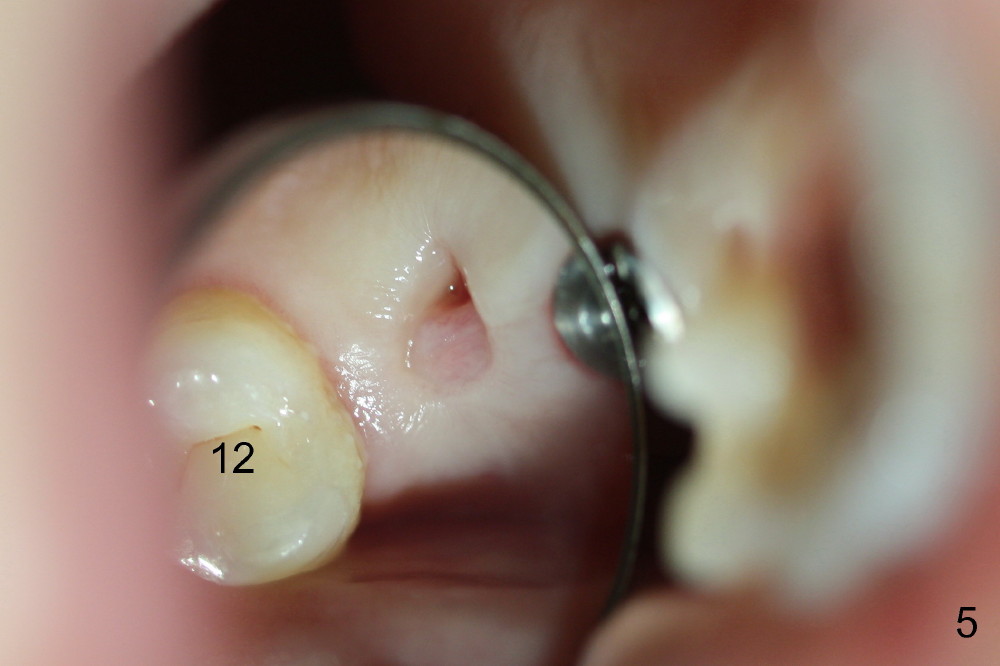

The patient returns for #13,14 implant placement. The ridge appears to be wide buccolingually (Fig.1 mirror view). A 4 mm tissue punch is used for access at the sites of #13 and 14. Osteotomy is initiated by using 3 mm trephine bur at the depth of 4 mm at both sites; 2 mm pilot drill is used to continue osteotomy at 8 mm deep at the site of #13. Sinus lift is accomplished by using tapered osteotomes 2,3 mm 6 mm deep, followed by 4.5x11 mm tap (Fig.2 T); 2 mm pilot drill (P) is reinserted into #13 osteotomy site with inadvertently penetrating the sinus floor. When the tap is removed from the site of #14, the sinus membrane is also found to be perforated. The sinus membrane at both sites is repaired by insertion of collagen dressing before bone graft. A 4x11 mm one-piece implant is placed at the site of #13 slowly hoping that it does not re-perforate the sinus membrane (Fig.3 O). Due to limited restorative height, the abutment portion of the one-piece is expected to be trimmed (Fig.4 O). In case of implant complication or failure, the implant may be difficult to be removed. Therefore the implant at the site of #14 is two piece one (Fig.4,5 I/A, 5x11 and 4x3 mm, respectively). The insertion torques for #13 and 14 are 35/40 and >60 Ncm. Immediate provisionals are canceled mainly because of patient's inability to open wide for long. Perio dressing is placed instead after adjustment of the height of the abutments. The patient experiences one episode of light nasal hemorrhage a few hours postop. Although the patient takes Amoxicillin for 1 week periop, the implant at the site of #13 dislodges 1 months postop (Fig.5). Immediate re-placement with a larger 2 piece one is canceled because of mild infection mesiobuccal to the implant at the site of #14 (Fig.6 >). Exploration around the latter implant reveals possible thread exposure in a small area. After copious irrigation with normal saline, Arestin is placed. Two months post exfoliation, the site is re-entered (Fig.7,8). There is a lingual defect. Osteotomy is initiated as buccal as possible. A 4.5x11 mm tapered tap penetrates the sinus floor without tearing the membrane (Fig.9). The same-sized implant is placed (25/30 Ncm) with sinus lift (Fig.10 *). The lingual defect is bone grafted. There is dehiscence lingually 7 days postop (Fig.11). Impression for final restoration is taken 1.5 months postop because of pending wedding. The crown has been in function for 2.5 months.